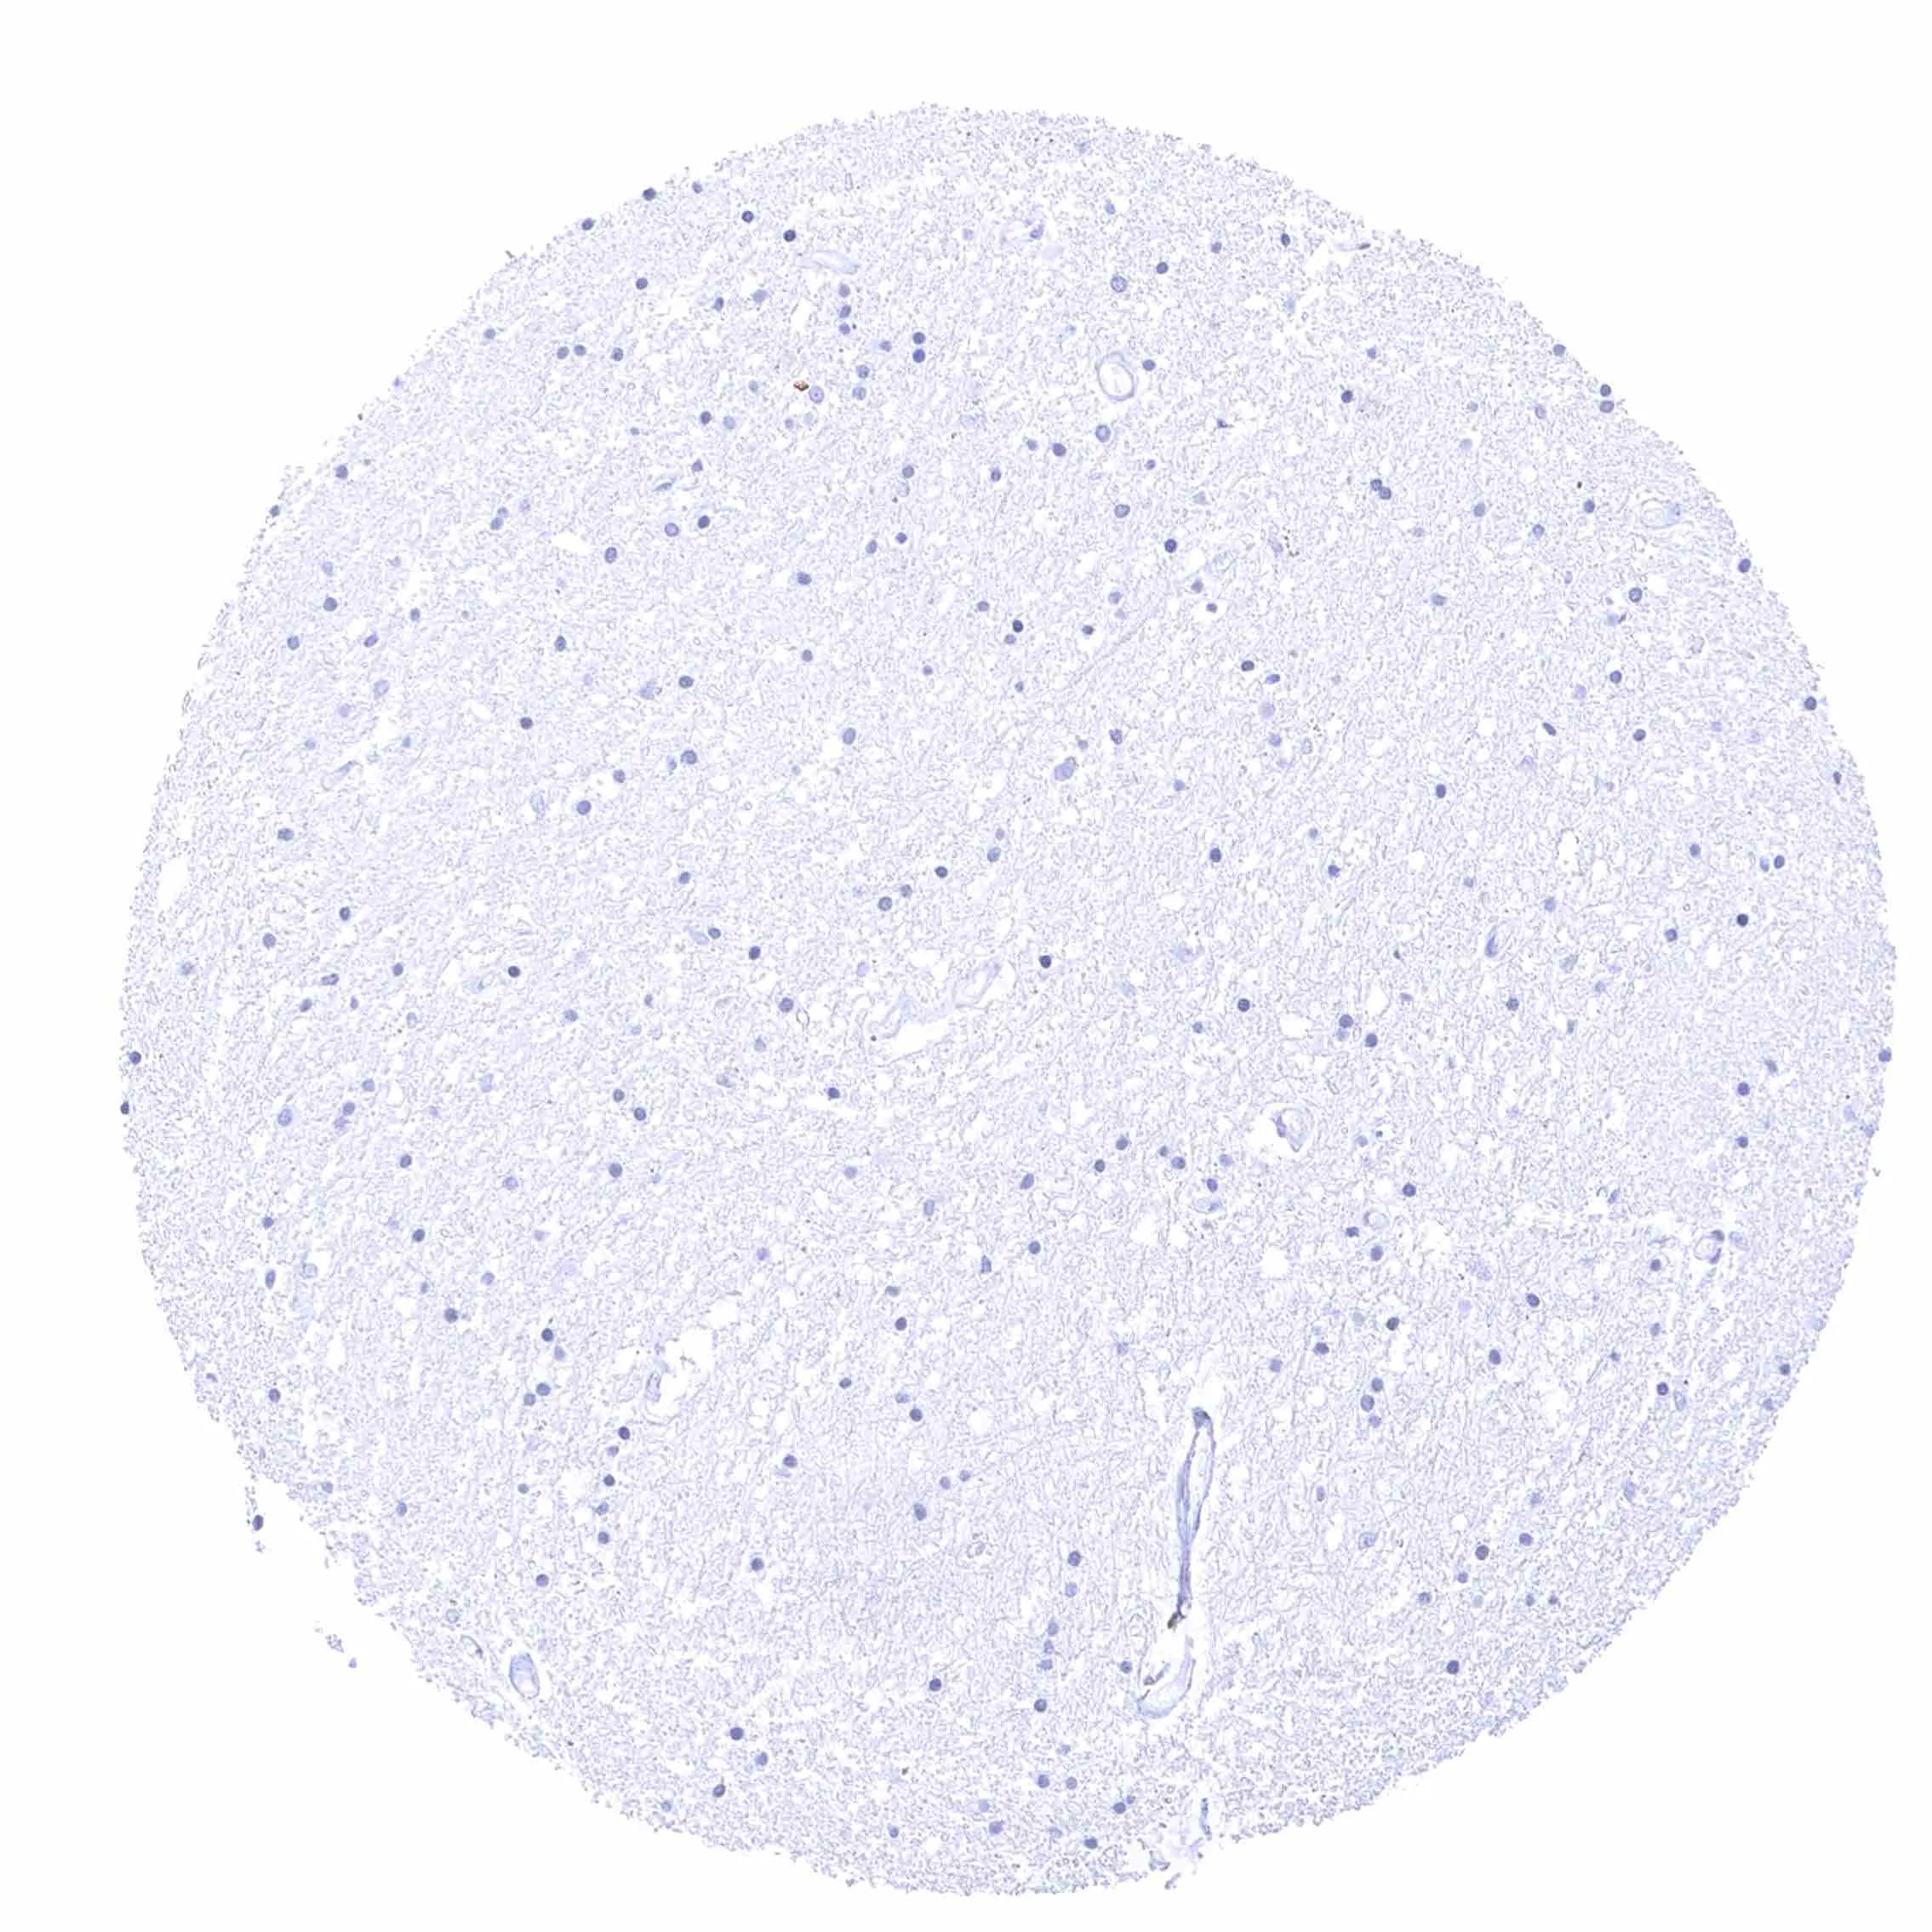

Cerebrum, grey matter

Cerebrum, white matter